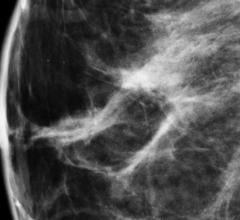

August 19, 2015 — A recent study by Mayo Clinic determined that adding molecular breast imaging (MBI) for women with ...

Grey Bruce Health Services’ regional hospital in Owen Sound, Canada, has adopted Carestream’s Vue PACS (picture archiving and communication system) and Vue Mammo workstations as part of its breast imaging program. The total solution includes Carestream’s digital breast tomosynthesis (DBT) module, full-field digital mammography (FFDM), breast ultrasound, breast magnetic resonance imaging (MRI), stereotactic biopsies and screening mammograms.

Despite decades of progress in breast imaging, one challenge continues to test even the most skilled radiologists ...